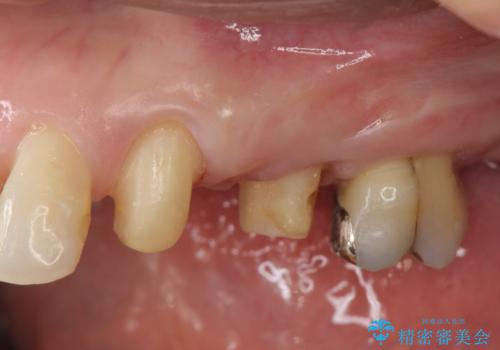

ブリッジの長期的な予後のためには支台となる歯の位置・清掃性が重要となりますが、今回ブリッジを製作するにあたり位置の悪い左上小臼歯を補綴前小矯正を行い位置を改善します。

補綴前小矯正について

矯正を行うことで歯を適切な位置に動かすことでより、清掃性に優れ長期的な予後を見込むことのできるブリッジを製作することができました。